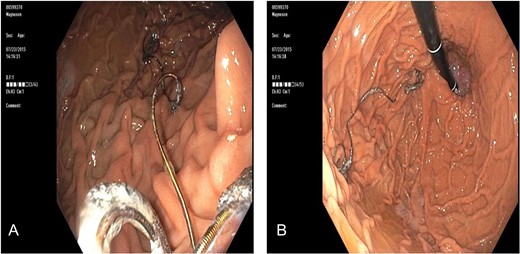

A 65 -year-old woman with a known history of multiple splenic and hepatic aneurysms was admitted to our hospital in October 2012 with acute abdomen. Abdominal computed tomography angiography showed rupture of splenic aneurysm with active extravasation of contrast and associated large left upper quadrant hematoma with small hemoperitoneum (Fig. 1). Visceral angiogram confirmed the presence of three fusiform aneurysms involving midsplenic artery (Fig. 2). The distal most aneurysm demonstrated large extravasation (Fig. 3). Coil embolization of the proximal and midsplenic artery aneurysm was performed using multiple Nester coils (Cook Medical, USA) with cessation of antegrade flow (Fig. 4). Attempt to access distal portion of the splenic artery was unsuccessful. She recovered well and was discharged 4 days later. In December 2016, she was admitted with dyspepsia and severe iron deficiency anemia requiring blood transfusion. A colonoscopy and upper endoscopy were performed which showed the presence of metallic coils in the stomach (Fig. 5). The patient subsequently underwent a combined upper endoscopy and laparoscopy. Three 5 mm ports were used to expose the lesser sac in event of hemorrhage during extraction of the coil endoscopically. An atraumatic bowel clamp was placed distal to the Treitz ligament to prevent insufflation of the small bowel. Upper endoscopy was performed using CO2 insufflation and the Nester coils were retrieved using rat tooth forceps (Fig. 6). There was no bleeding in the lesser sac after removal of the coils. A leak test was performed to rule out gastric perforation. She had an uneventful recovery and was discharged the next day.

(A) Endoscopy showed wire strands in the fundus of the stomach and (B) occluding the pylorus.

Endoscopic retrieval of coils assisted with laparoscopic visualization of lesser sac.